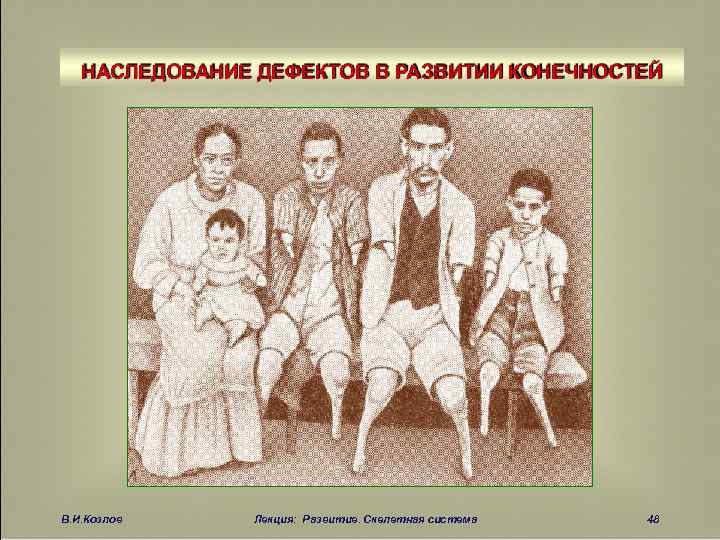

НАСЛЕДОВАНИЕ ДЕФЕКТОВ В РАЗВИТИИ КОНЕЧНОСТЕЙ В. И. Козлов Лекция: Развитие. Скелетная система 48